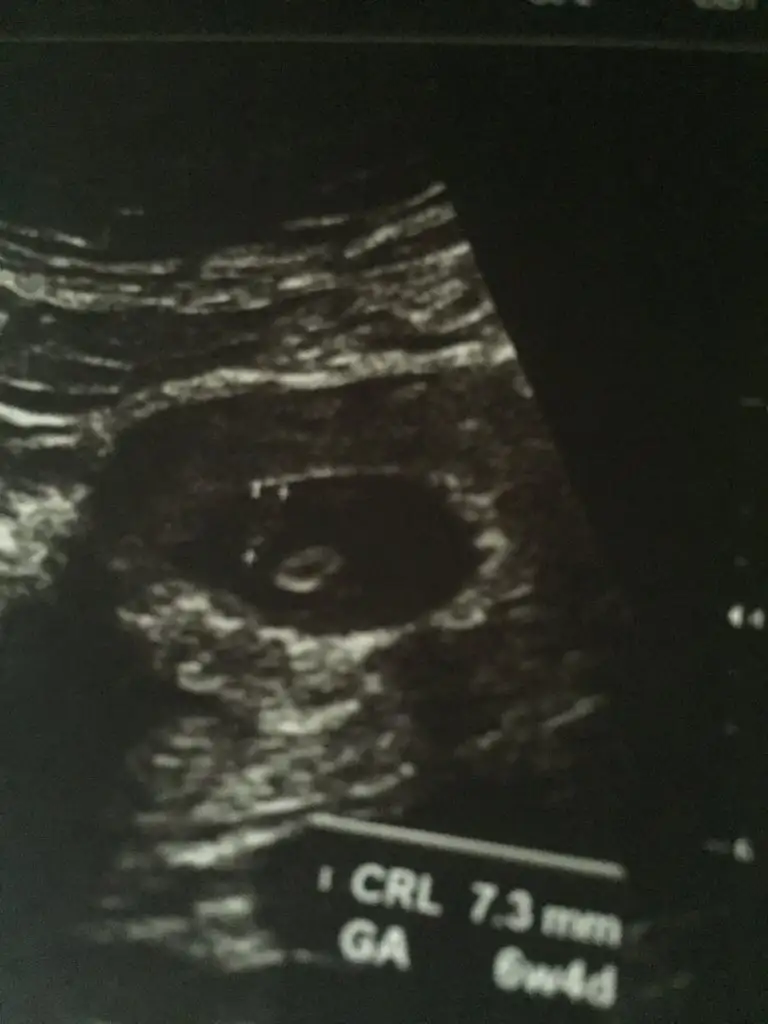

bugun bende kontrole gıdıcem

tahmınımce bugun 6+2 oldum

ama bılmıyorum bakalım ne soylecek doktor

cok merak edıyorum

sizlerede sonucu bıldırırım kızlar

cok guzel ya heycanlı bı durum

IMG_20191216_145210.webp

4+3'ken gittim doktor şu işaretli alanda bebeğin yer alacağını söyledi şu an için boşmuş ama. Benim hesabıma göre 4+3 iken doktora göre iki haftalık şu an. 10 gün sonrasına kontrol verdi, 5+6'ya denk geliyor. Umarım kalp atışı duyabilir ve bebeği görebilirim.